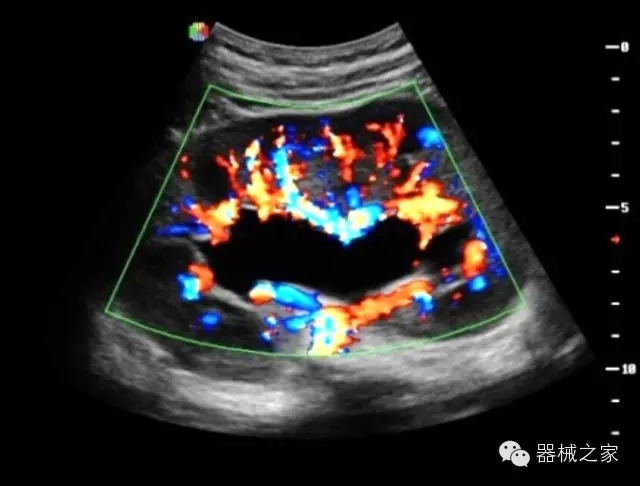

臨床圖片賞析

·智能微血流成像技術(shù):智能微血流捕捉技術(shù)可以提取出隱藏在背景噪聲中的弱血流信號,大大提高低速血流的敏感性;

·移植S40高端臺式彩超高端平臺技術(shù),滿足超聲科腹部、淺表、婦產(chǎn)科、心血管、肌骨等應(yīng)用,提供超聲科完美解決方案;